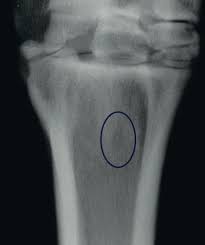

Elevating the plantar angle (via wedges, heel platforms, or graduated shoes)

Reducing digital hyperextension and hence load at the PSL origin

Optimizing breakover and caudal support

Addressing mediolateral imbalances to reduce torque

Incorporating frog support or bar shoes in horses with collapsed heels

Dynamic shoeing protocols should be guided by radiographs, gait analysis, and ongoing postural observation, with frequent reassessment and gradual tapering.

Duo eclipse elevated bar shoe used by the author in acute cases DPSL injuries